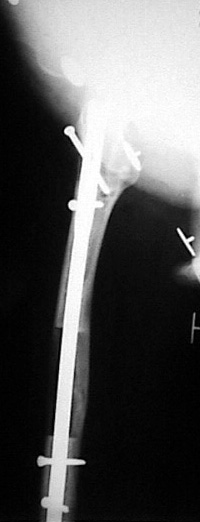

İntramedüller çivinin yerleştirilmesi ve osteotomi: Hasta traksiyon masasına supin pozisyonda yatırılır ve sağlam bacak altta olacak şekilde bacaklar makas pozisyonuna alınır. Standart yolla piriformis çukurundan medulla içine girilir ve kılavuz tel üzerinden kullanılacak çividen 1.5 mm daha kalın oyucu ile medulla oyulur. Proksimal femur, çivinin proksimali daha kalın olduğu için daha kalın oyulur. Radyografide osteotomi hattı planlaması yapılır. Planlama yapılırken uzatma sonunda distalde en az 8 cm. çivi kalması stabilizasyon için gereklidir. Kortikotomi perkütan olarak kortikotom ile tamamlanır. Daha sonra kılavuz tel çivinin boyunu ölçmek için distale ilerletilir. Uygun boyda intramedüller çivi çakılır. Son olarak çivi proksimalden kilitlenir ve bir adet dren konarak ameliyatın birinci kısmı tamamlanır.

Eksternal fiksatör uygulanımı: İntramedüller çiviye değmeden aşağıya ve yukarıya üçer adet Schanz vidası gönderilir. Vidalarla çivi arasında en az 1 mm den fazla mesafe olmalıdır.

Biz son zamanlarda, seçilmiş vakalarda, uzatma sonrası uzunluğu ve “alignment’ı” korumak amacı ile unilateral dinamik aksiyel fiksatör ve kilitli intramedüller çivi kombinasyonunu tercih etmekteyiz. Bu yöntemin ön şartları medullanın en dar çapının 7 mm.’den geniş olması ve uzatma sonrası distalde en az 8 cm. uzunluğunda çivi kalabilmesidir. İntramedüller çivi hem uzatma esnasında femurun üzerine gelen makaslama ve bükülme kuvvetlerini nötralize etmekte hem eksternal fiksasyon süresini kısaltmakta, hem de yeni oluşan kemiği kırıklara karşı korumaktadır. Serimizde bir vakada subtrokanterik femoral osteotomi yapılmıştır. İntramedüller çiviye rağmen varus angulasyonu oluşması yönünde bir dezavantaj tespit etmedik.

İlizarov, distraksiyon osteogenezisi için endosteal kan dolaşımının önemini vurgulamıştır. Biz tüm vakalarımızda femuru oyarak intramedüller çiviyi çaktık; buna rağmen hiçbir vakada kallus oluşma süresi tahminimizden daha uzun olmadı. Bu yüzden medüller dolaşımın bozulmasına bağlı yeni kemik oluşma hızında bir yavaşlama olmadığını düşünüyoruz. Oyma sonrası meydana gelen revaskülarizasyon, intramedüller çivili fiksasyon stabilitesi ve erken fonksiyonel yüklenme bu gerçeğin temelini oluşturmaktadır. Eksternal ve internal fiksasyon yöntemlerinin kombine kullanımının potansiyel dezavantajları kan kaybının artması, intramedüller infeksiyon, yağ embolisi olasılığı ve aşırı metal yüküdür. Bunların içinde en çok korkulan problem bir çivi dibi infeksiyonun tetikleyeceği derin intramedüller infeksiyondur (panosteomyelit). Bizim serimizde bu yönde hiçbir komplikasyon gelişmemiştir. Bu olası komplikasyonun önlenmesi amacı ile uzatma sonundaki kilitleme medialden yapılmalıdır; ayrıca intramedüller çivi ve eksternal fiksasyon pinlerinin teması önlenmelidir.